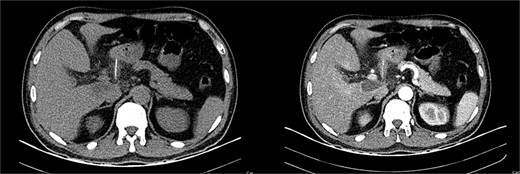

It unveiled a linear hyperdensity behind a thickened stomach wall in the lesser sac, in close contact with the pancreas and duodenum; it had areas of surrounding fat stranding and tissue thickening without pneumoperitoneum. A perforation caused by a fishbone was suspected (Figs 1 and 2).

(A) CT, the fishbone is seen in the lesser sac. (B) Contrast enhanced CT, the fishbone is seen free in the lesser sac in close contact to the pancreas.

CT, the location of the fishbone in the lesser sac embedded in the pancreas.